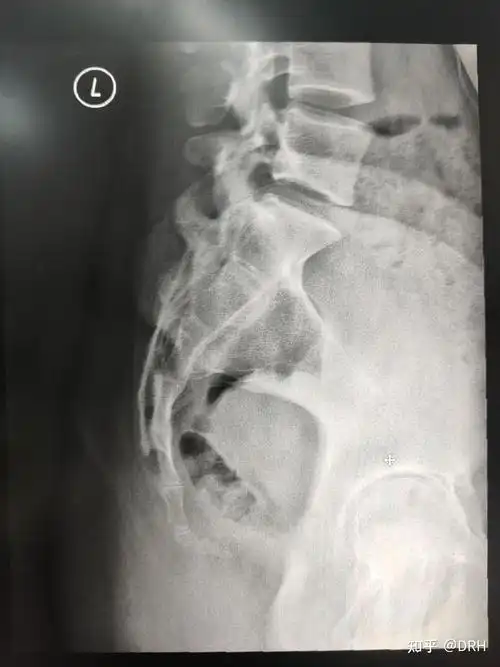

骶尾椎影像报告怎么写? - 知乎